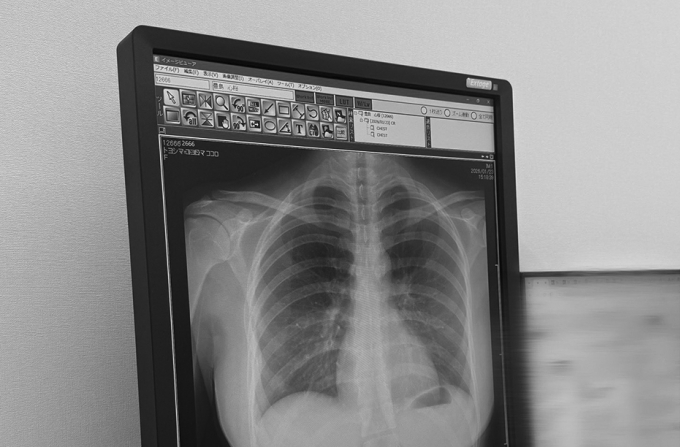

Bức ảnh chụp X-quang phổi của Kokoro Toyoshima bất ngờ gây sốt mạng xã hội nhờ để lộ vóc dáng gợi cảm, thu hút hàng chục triệu lượt xem chỉ sau hai ngày.

Sự việc bắt đầu khi nữ người mẫu 22 tuổi đăng tải tấm phim X-quang lên mạng xã hội X hôm 23/1, kèm thông báo ngắn gọn về kết quả kiểm tra sức khỏe: “Phổi của tôi rất sạch”. Theo Oricon News, mục đích ban đầu của Toyoshima chỉ là cập nhật tình hình sức khỏe cho người hâm mộ.

Tuy nhiên, bức ảnh đen trắng nhanh chóng lan truyền với tốc độ chóng mặt, đạt hơn 43 triệu lượt xem và 58.000 lượt thích tính đến ngày 25/1. Điểm thu hút sự chú ý không nằm ở kết quả y tế mà là cấu trúc xương và đường cong cơ thể hiện rõ trên phim chụp. Nhiều khán giả nhận xét hiếm thấy tấm phim X-quang nào vẫn lột tả được trọn vẹn vóc dáng người chụp, đặc biệt là khuôn ngực cup H nổi tiếng của nữ thần tượng.

Hàng nghìn bình luận bày tỏ sự ngạc nhiên trước hình ảnh lạ lẫm này. “Đến ảnh X-quang cũng toát lên vẻ quyến rũ”, một tài khoản nhận xét. Bên cạnh những lời khen về ngoại hình, một số người xem có kiến thức y khoa cũng cảnh báo Toyoshima về dấu hiệu cong vẹo cột sống nhẹ nhìn thấy trên phim, khuyên cô nên chú ý tư thế sinh hoạt để bảo vệ sức khỏe.

Các bác sĩ chấn thương chỉnh hình cho biết, phim X-quang phổi thẳng ngoài việc khảo sát nhu mô phổi, tim và lồng ngực, còn là công cụ hữu hiệu để phát hiện sớm các bất thường về khung xương. Trên phim chụp thẳng, cột sống bình thường sẽ là một đường thẳng đi từ cổ xuống xương cùng. Nếu các đốt sống bị xoay hoặc lệch trục sang trái hoặc phải, đây là dấu hiệu của vẹo cột sống.

Qua trường hợp của Toyoshima, các chuyên gia khuyến cáo người dân nên tận dụng các đợt khám sức khỏe định kỳ để rà soát kỹ hệ vận động. Nếu phát hiện cột sống có dấu hiệu cong vẹo trên phim X-quang phổi, người bệnh nên chụp thêm phim X-quang cột sống toàn trục để bác sĩ chuyên khoa đánh giá chính xác mức độ và đưa ra phác đồ điều trị kịp thời.